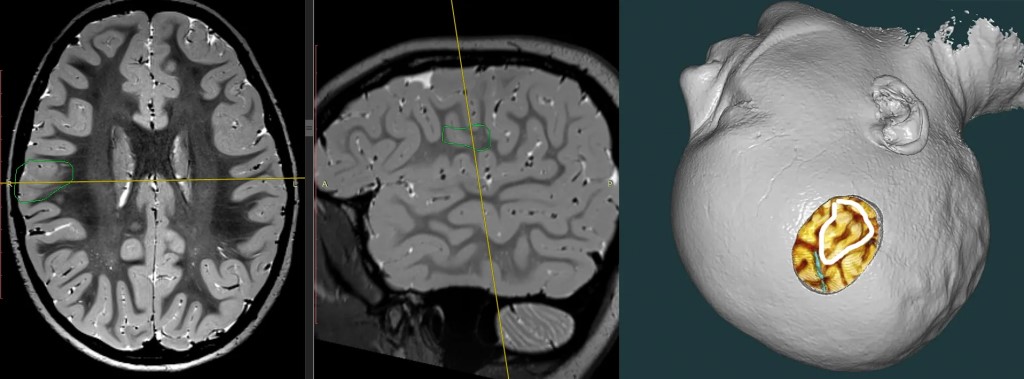

Фото 3D-печать активно внедряется во все аспекты нейрохирургии: как напечатали выздоровление 9-летнего пациента 🧠 В НМИЦ нейрохирургии имени Бурденко аддитивные технологии стали не просто экспериментом, а рабочим инструментом. Особенно в сложнейших операциях — например, при лечении эпилепсии. История пациента 👦 9-летний ребёнок страдал от фармакорезистентной эпилепсии с младенчества. Лекарства не помогали. После долгого обследования (МРТ высокого разрешения + ночной ВЭЭГ-мониторинг), который проведён в НМИЦН нашли причину — фокальная корковая дисплазия. Это врожденный порок развития коры головного мозга. Главная сложность 🚨 Очаг находился в опасной близости от зон, отвечающих за речь и движение левой руки. ❌Ошибаться нельзя. Технологии на максимум 🖨️ Специалисты не просто спланировали операцию по снимкам МРТ — они послойно визуализировали все структуры, а в лаборатории аддитивных технологий центра напечатали на 3D-принтере персонализированное устройство. С виду простое, но именно оно позволило: — уменьшить размер операционной раны; — действовать максимально точно и бережно. Ход операции 🔎 Под контролем нейрофизиологического мониторинга и с использованием микрохирургической техники дисплазию удалили. После операции ожидаемо возник легкий неврологический дефицит, но к выписке он практически полностью исчез. Результат ✅ Контрольная МРТ подтвердила: очага больше нет. С момента операции приступы не возвращались. Ребёнок выписан домой в удовлетворительном состоянии. Ещё один пример, когда инженерия, нейрофизиология и хирургия работают в одной связке — ради будущего без болезни. #нмицбурденко #ниинейрохирургии #ниибурденко